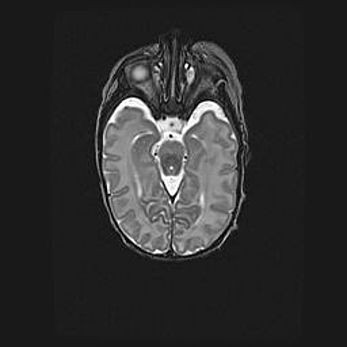

Лейкомаляция с кистозно-глиозной дегенерацией головного мозга.

Возраст: 2 месяца 25 дней

Вес: 6400 г

Окружность головы: 40 см

Срок гестации: 41 неделя

Лейкомаляцию относят к ишемически-гипоксическим повреждениям головного мозга, диагностируемым у новорожденных. При лейкомаляции в головном мозге обнаруживают очаги некроза, возникшие после тяжелой гипоксии и нарушения кровотока. В процессе морфогенеза очаги проходят три стадии: 1) развития некроза, 2) резорбции и 3) формирования глиозного рубца или кисты. Перивентрикулярная лейкомаляция (ПЛ) встречается примерно в 12% случаев среди новорожденных, обычно – у недоношенных детей, причем, частота ее зависит от массы, с которой младенец появился на свет. Наибольшее число малышей страдает лейкомаляцией, если масса при рождении 1500-2500 г.